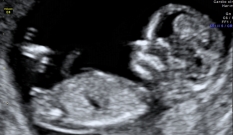

O ultrassom do primeiro trimestre Embora possa ser feito um pouco antes ou um pouco depois, hoje em dia, o momento mais comum para fazer um ultrassom de primeiro trimestre é quando se completam 12 semanas. Isso porque, neste momento, o desenvolvimento anatômico e o tamanho do feto permitem comprovar que a maioria dos órgãos se formaram adequadamente.

Um ultrassom de alto nível neste momento pode detectar até 60-70% dos possíveis problemas de malformação que aparecerão na gestação. A outra medição que se faz é a da translucência nucal, o líquido que todos os fetos têm na nuca.

A espessura da nuca do feto é medida e seu valor é utilizado como parte do rastreamento genético do primeiro trimestre. Como já comentamos, esse conjunto de exames permite estimar o risco de uma anomalia no número de cromossomos (tecnicamente definida como aneuploidias), especialmente a trissomia do cromossomo 21 (síndrome de Down). Para o cálculo do risco, o valor da translucência nucal é combinado com a idade materna e os valores de dois hormônios (beta-hCG e PAPP-A), identificados em análise do exame de sangue.

Também é possível usar a informação desse ultrassom do primeiro trimestre para incluir no rastreamento do primeiro trimestre o cálculo do risco de pré-eclampsia.